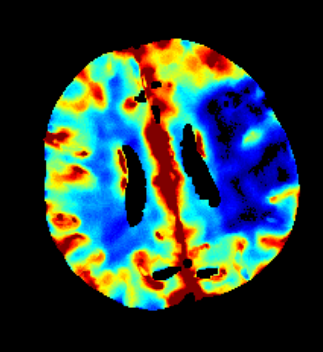

Furthermore mRay is capable of performing image processing tasks such as finding, visualizing and quantifying anomalies in tissue. In particular the image analysis module mRay VEOcore may be used to perform an automated processing of brain images from imaging modalities such as CT, CT-Perfusion, or MRI including a Diffusion Weighted Imaging (DWI) Module. As a result, changes in contrast over time are visualized as colored perfusion maps, including flow related parameters and tissue blood volume quantification.

The perfusion analysis of brain imaging data visualizes and quantifies tissue that is less supplied with blood (penumbra), oxygen deprived tissue caused by obstructed blood flow (core tissue) and the mismatch ratio between the two. The calculated values can be used to support decision making based on an assessment of the extent of tissue damage.

16.1. Overview

VEOcore is a fully automated image processing tool to calculate quantitative measures of affected brain tissue and healthy tissue. Therefore, this manual covers the instructions on how to interpret the results. It’s an extension the mRay Server application and the results can be viewed inside the mRay Client. Furthermore processed results can be automatically forwarded to the PACS.